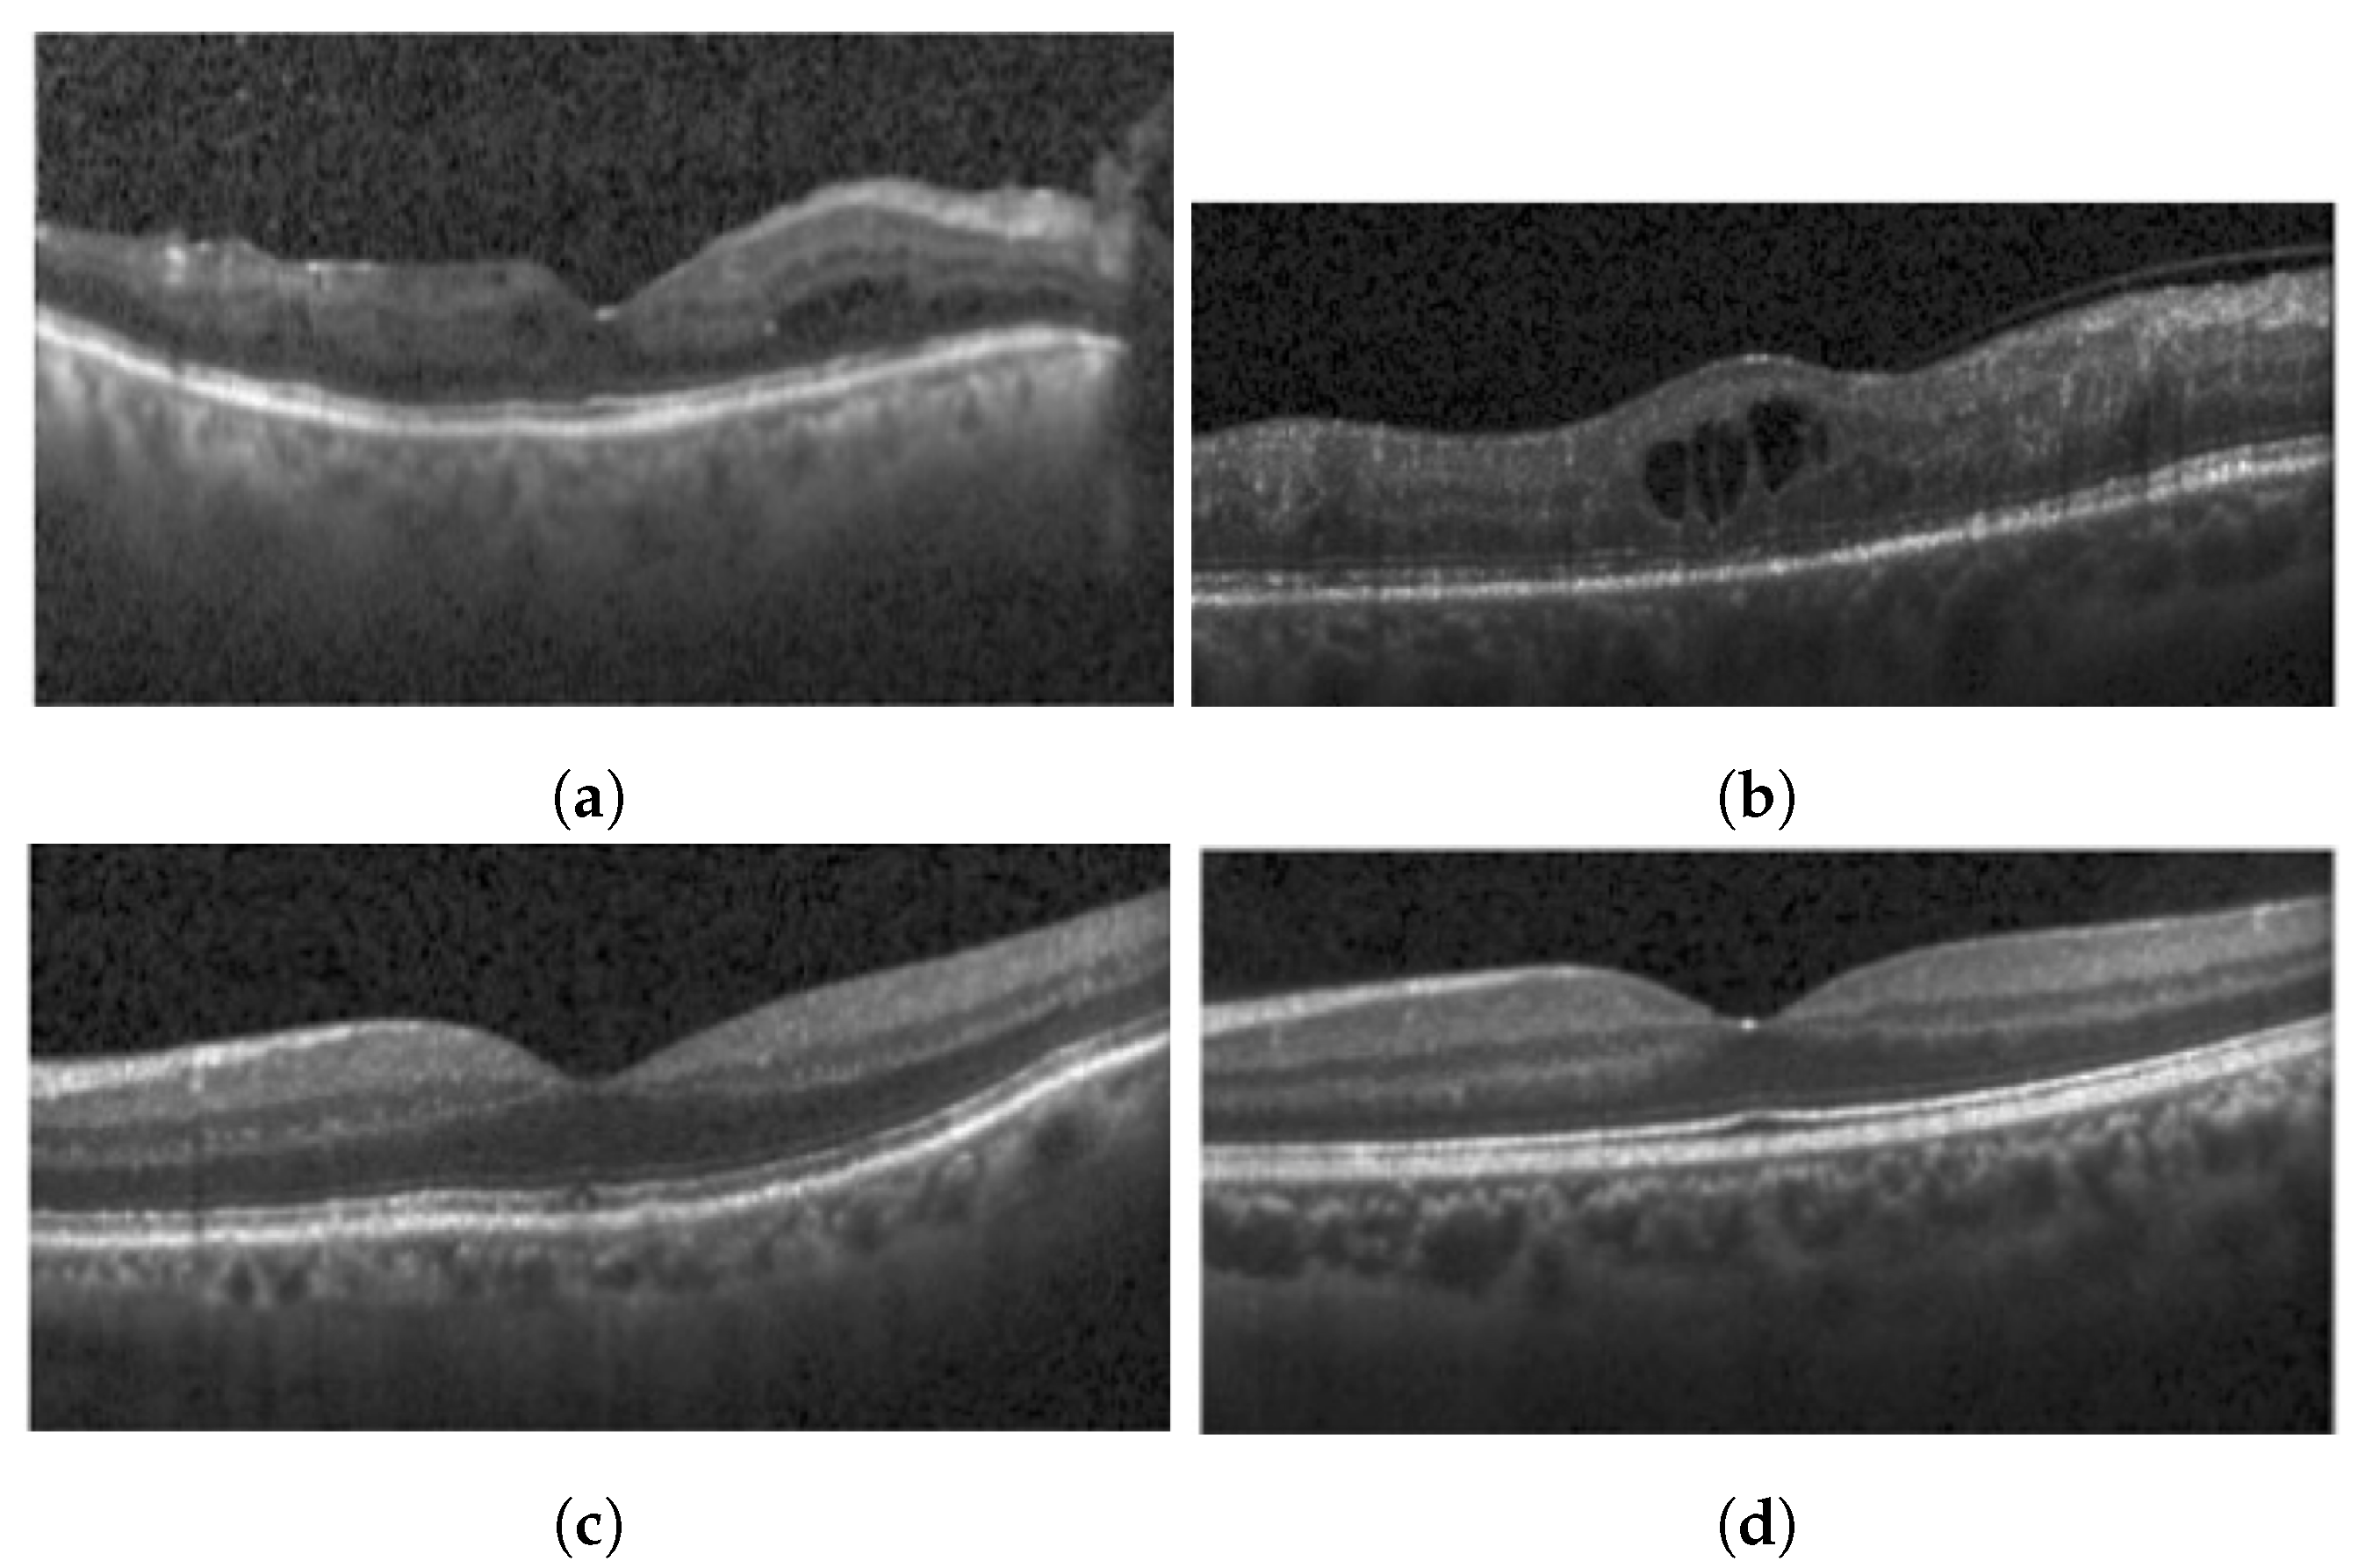

2.2. Hyperreflective Foci

2.3. Cystoid Spaces

3.1.2. Hyperreflective Focii (HRF)

3.1.3. Cystoid Space